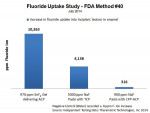

According to the manufacturer, a “pea-sized” (0.25 grams) portion of Enamelon Preventive Treatment Gel (970 ppm fluoride content) (Figure 5) contains 0.24 mg of fluoride, versus 1.25 mg of fluoride in an identical volume of paste in a typical 5,000-ppm fluoride ion prescription-strength toothpaste. When these two products were tested for enamel fluoride uptake (using method #40 in the US FDA Anticaries Drug Products for OTC Human Use, Final Monograph testing procedures), the Enamelon Preventive Treatment Gel (970 ppm F- ion) provided nearly 2-½ times greater increase in fluoride uptake into incipient lesions in enamel than the 5,000-ppm fluoride ion prescription-strength toothpaste. Additionally, the Enamelon Preventive Treatment Gel provided a 30 times greater increase in fluoride uptake into incipient lesions in enamel than a 900-ppm fluoride ion product containing casein phosphopeptide-amorphous calcium phosphate (CCP-ACP) (Figure 6) (independent testing data: Therametric Technologies, Inc., 2014).

It is important to explain the nature and use of these concentrated stannous fluoride products to parents and especially to children old enough to understand the purpose of these protocols. To date, patients have reported that the Enamelon products have a pleasant taste, and parents have been compliant with having their children use the new gel and toothpaste. In view of the lower amount of fluoride content in the treatment gel, the increased fluoride uptake shown in Figure 6, and the increased resistance to acid challenge of treated enamel as shown in Figure 7, the authors expect Enamelon Gel to be a valuable preventive dentistry adjunct in the overall care of high-caries-risk children and teenagers, especially those wearing fixed orthodontic appliances.